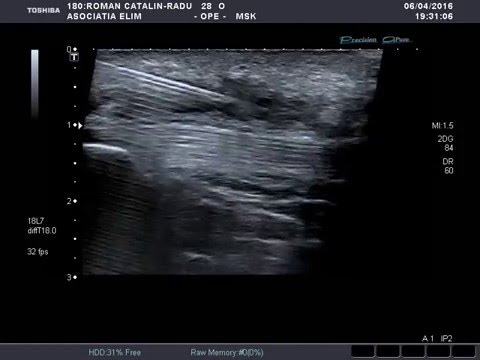

Pentru alte sensuri, vedeți ozon (dezambiguizare). Tvr craiova 15.481 views3 years ago. A facut cineva infiltratii cu ozon la spitalul municipal? .cu ozon, denumite si terapia cu ozon, reprezinta o forma de tratament alternativ pentru cresterea cantitatii de oxigen din organism, prin introducerea ozonului in interiorul coloana medicala. Sedinta include infiltratii subcutanate cu ozon pentru tratarea durerilor de generate de coloana vertebrala/spate, dureri articulare la genunchi, solduri, umeri, maini, glezne + dureri de cap etc.